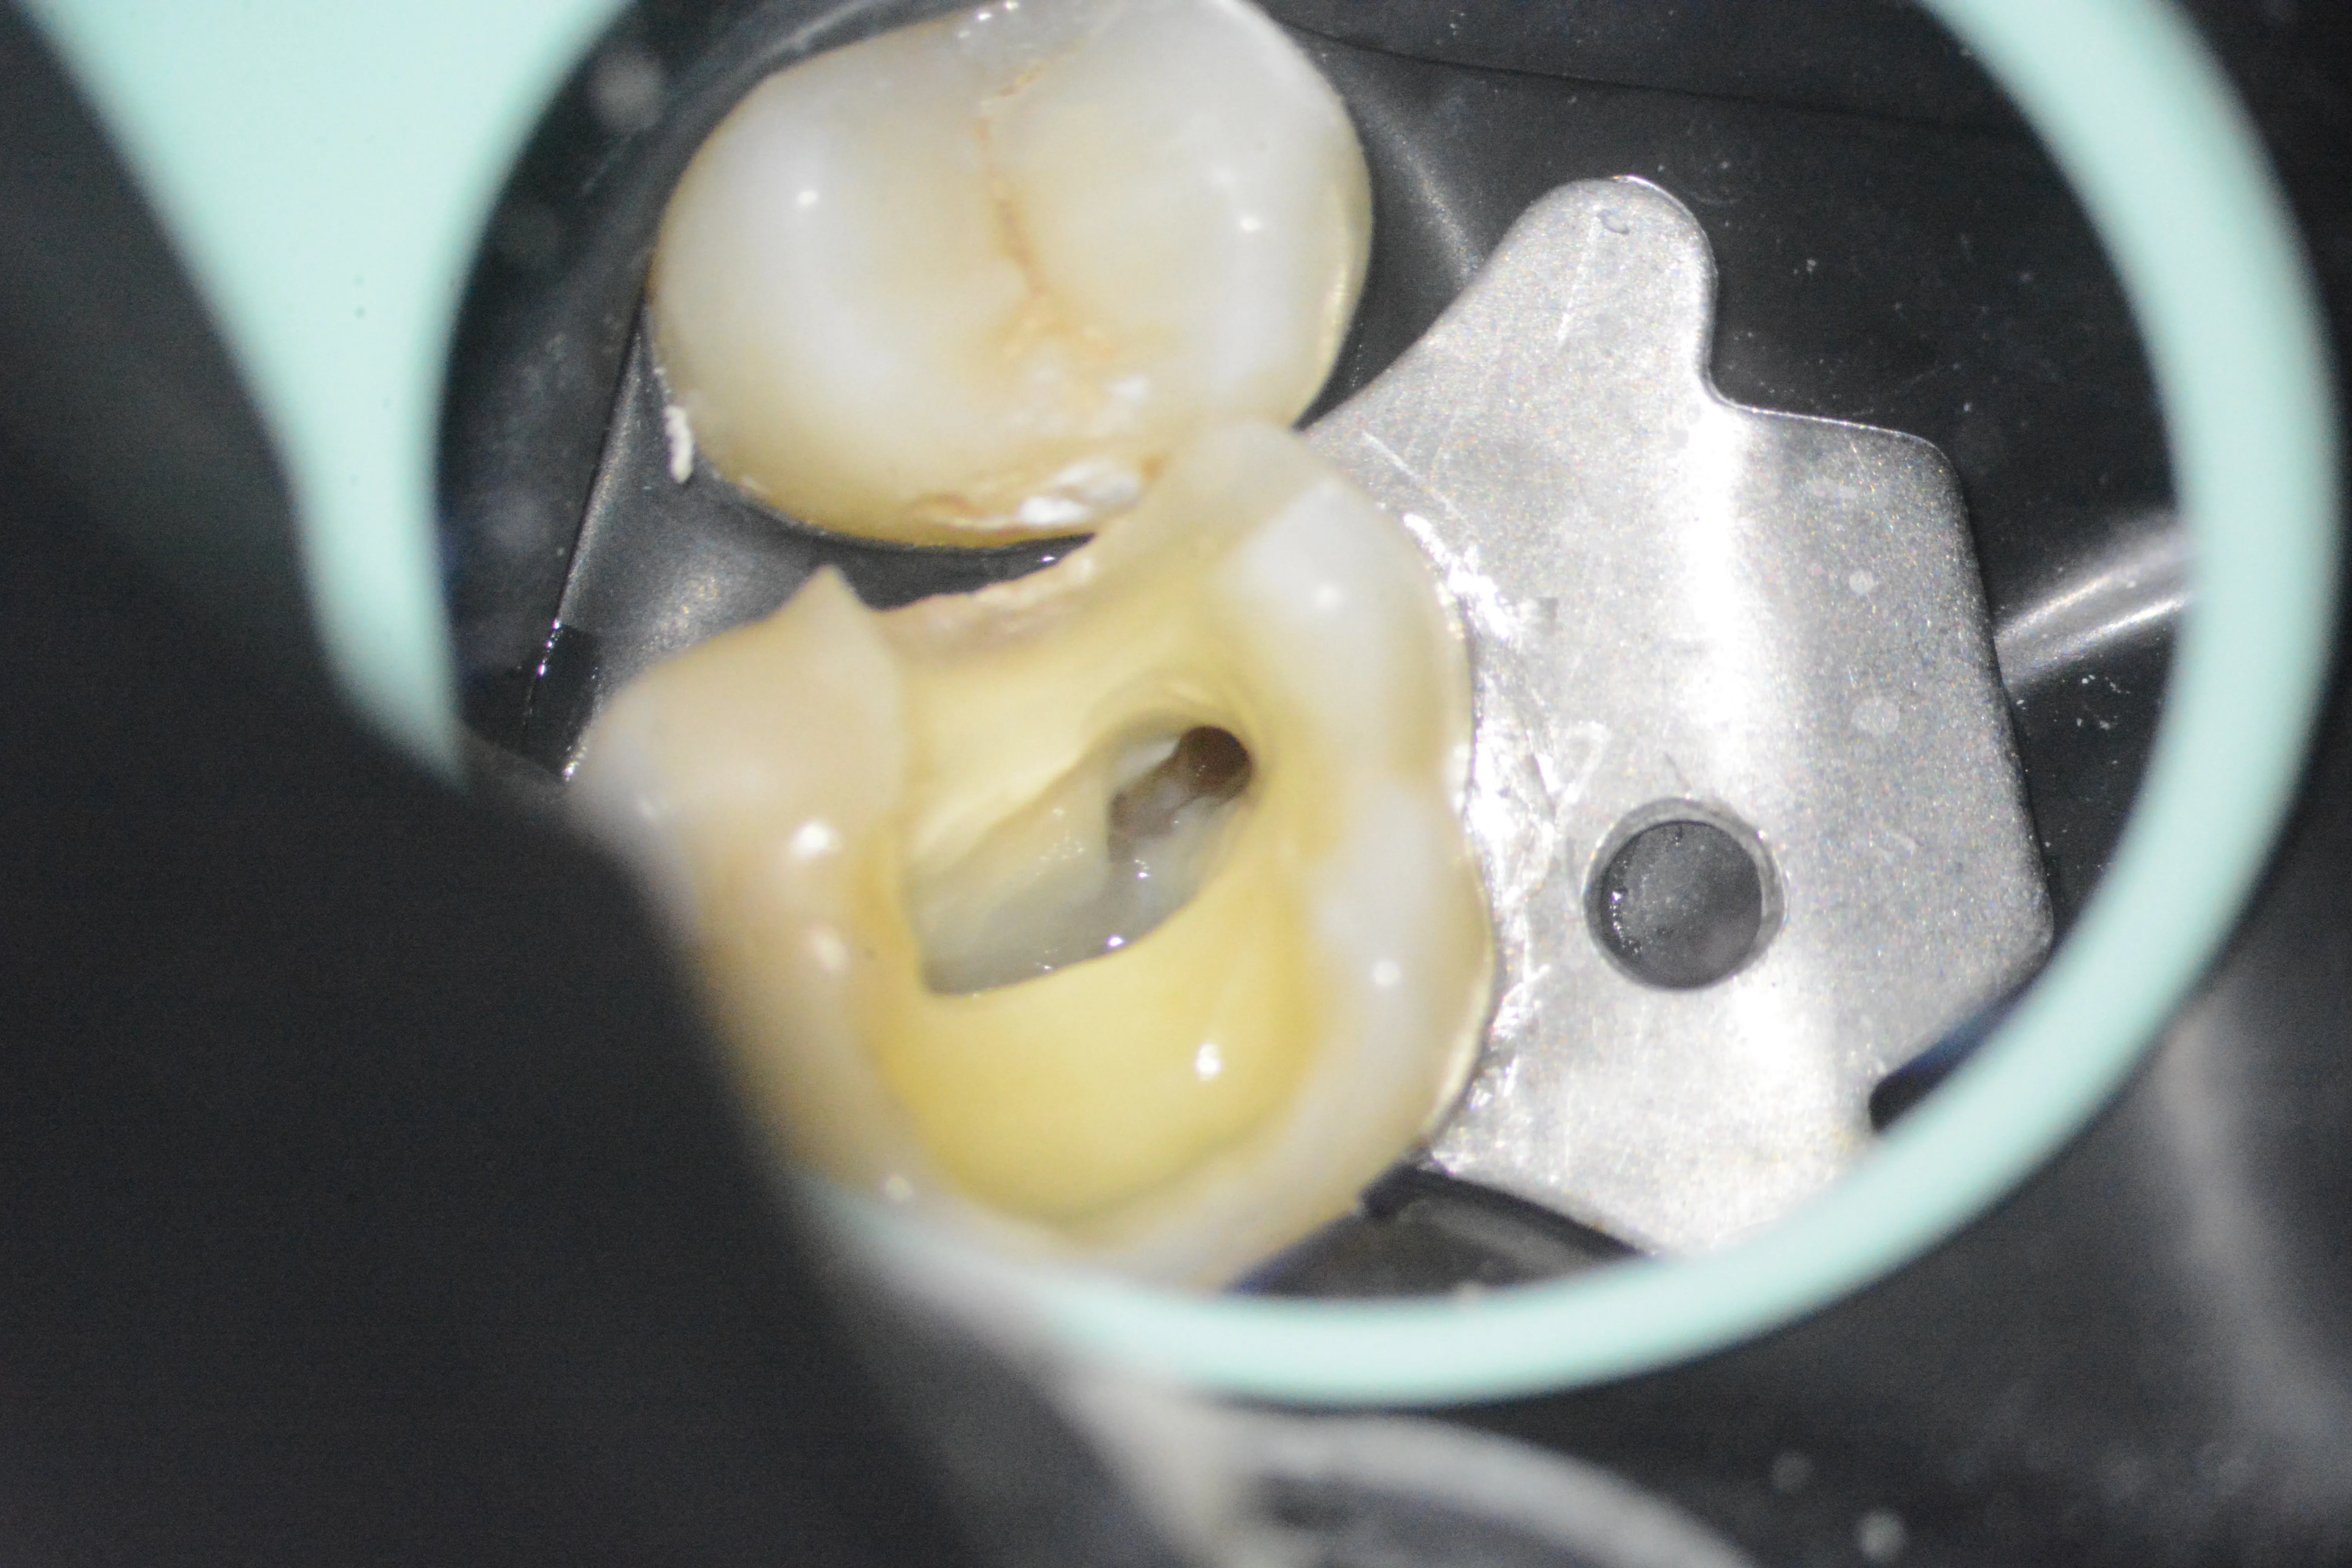

2 – Aspect clinic inițial